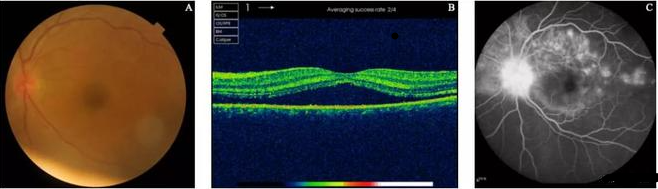

交感眼(左眼)的影像学检查